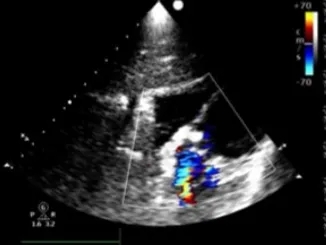

左右盘面展开并锁定

左侧伞盘出鞘为球状,牵拉成型线后形态佳,后展开右盘,封堵器呈现“长哑铃状”,主动脉瓣少量反流。

轻轻牵拉成型线使封堵器成型,牵拉后左伞盘被拉进瘤腔内。

左右盘展开后,封堵器未锁定时造影可见封堵器中间少量反流,主动脉瓣少量反流。

牵拉成型线锁定后,分流消失,主动脉瓣反流消失。

封堵器锁定后呈“蝴蝶状”明显盘状形态,室水平分流完全消失,主动脉瓣反流消失。